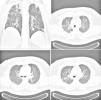

The consolidation areas had a peribronchovascular and subpleural predominance and were found mainly in the middle and upper zones of the lung (Fig. 2). Reticular opacities were found in six cases. The most outstanding CXR and chest CT features of the disease were basal and axial interstitial-alveolar consolidation and ground-glass opacities (Fig. 3): the extent of disease was greater in Group 1 (patients requiring mechanical ventilation) with a greater number of lobes involved and a greater CXR score (p<0.001). Airway thickening and dilatation, small airway involvement with centrilobular nodules and tree-in-bud opacities was not found.

The most common chest CT abnormalities of pandemic H1N1 influenza virus infection were multifocal consolidation and ground-glass and more rarely poorly defined nodules with upper lobe predominance.18 The predominant findings in our study were bilateral consolidation and reticular opacities similar to those reported in previous literature and the predominant computed tomographic findings were ground-glass opacities and areas of consolidation.8,14,19 Multifocal bilateral distribution and Opravil CXR score were directly correlated with the severity of the illness: actually all the patients who underwent invasive or non-invasive mechanical ventilation had multifocal bilateral opacities and a higher CXR score. Secondary bacterial pneumonia usually presents a pattern consistent with bronchopneumonia, including lobular, subsegmental or segmental consolidation.20 In our case-series only one patient presented a bacterial co-infections (Staphylococcus aureus MRSA) with radiological findings of lobar pneumonia (Fig. 4).